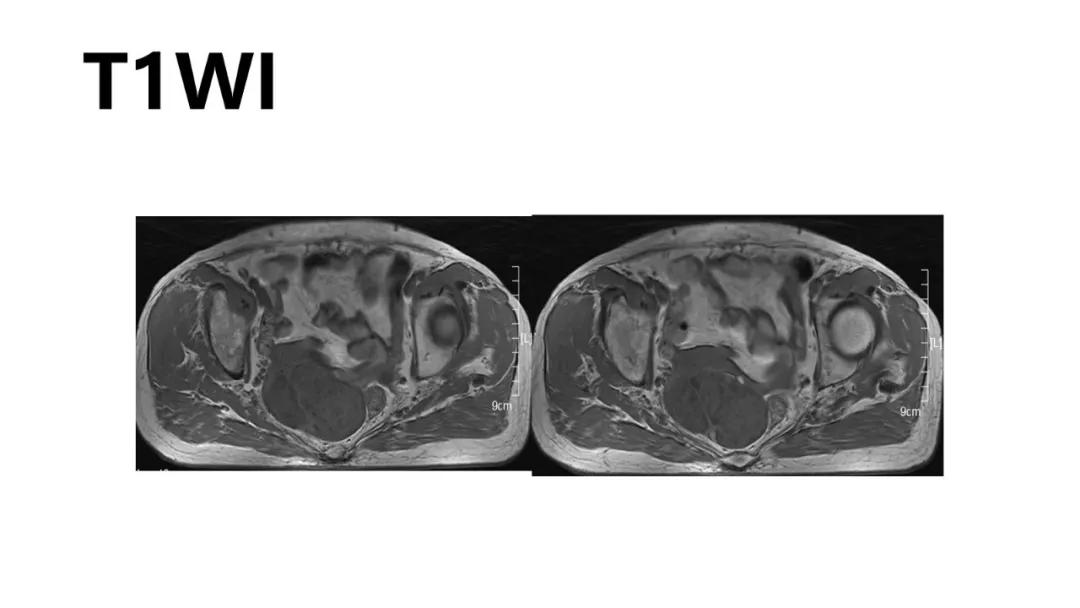

病理:左侧卵巢卵泡膜-纤维瘤